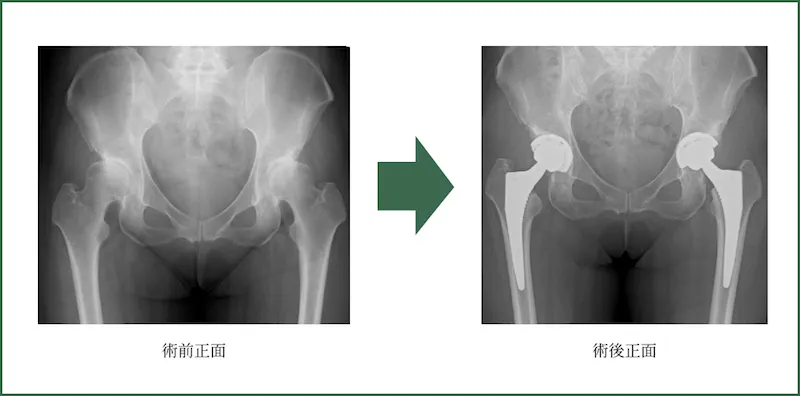

人工股関節置換術

(THA: Total hip arthroplasty)

全身シールド装置(サージカルヘルメット)を使用しております。

手術時間:平均55分

出血量:平均50ml

年間件数:100件程度(2024年度見込み)

※年間300件以上執刀する平澤医師と野木医師、古賀医師が担当